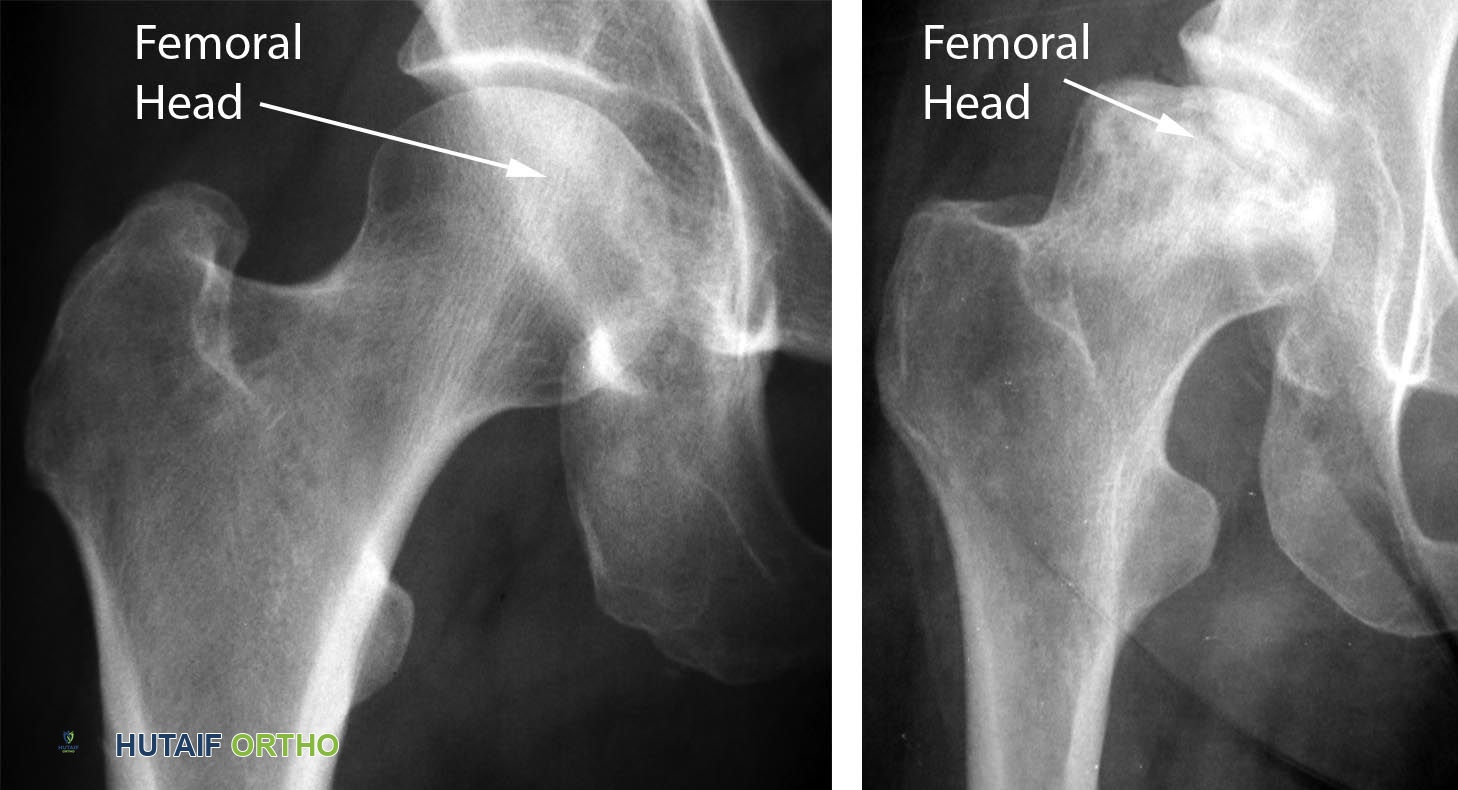

- تُؤخذ صور الأشعة السينية للورك من زوايا مختلفة (AP pelvis و frog-leg lateral views).

- في المراحل المبكرة جدًا (ARCO 0, I)، غالبًا ما تكون الأشعة السينية طبيعية ولا تُظهر أي تغييرات.

في المراحل اللاحقة، قد تُظهر الأشعة السينية علامات مميزة مثل:

- علامة الهلال (Crescent Sign): خط شفاف تحت الغضروف يُشير إلى كسر تحت الغضروف.

- انهيار رأس عظم الفخذ: تسطح أو تدرج في السطح المفصلي لرأس الفخذ.

- التصلب والتكيسات: مناطق ذات كثافة عظمية متزايدة أو مناطق شفافة داخل رأس الفخذ.

- التهاب المفاصل الثانوي: تضيق في المسافة المفصلية، نتوءات عظمية (Osteophytes)، وتكيسات تحت الغضروف.